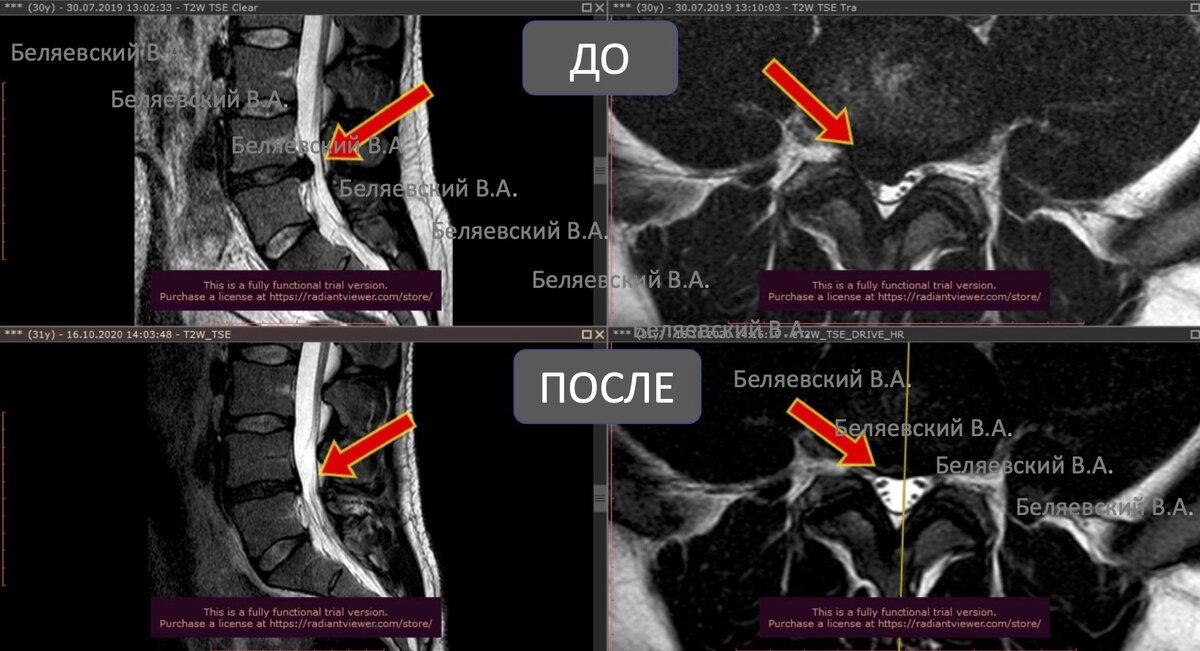

Резорбция грыжи межпозвонкового диска что это такое